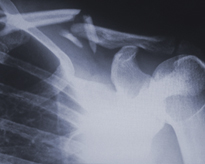

OSTEOPOROSIS

Osteoporosis is a chronic and progressive disease which makes the bones weaker and liable to break more easily. It is known as a "silent disease", as the loss of bone mass occurs without presenting any symptoms or ailments. Patients are therefore unlikely to discover that they have this disease until they break a bone due to a fall or pulled muscle. This condition presents in elderly people in particular, the majority of whom are women. It is the main cause of prolonged hospital admissions in women over 45 years of age.

Alter Médica wants to help the healthcare professional who looks after the bone health of their patients, providing them with treatments that help in the prevention and treatment of osteoporosis and deficiency states of calcium and vitamin D.